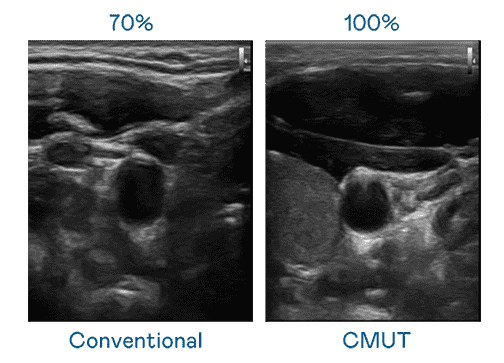

CMUT 技术是一种用电容式微机电元件来产生超音波讯号的技术。。。。与传统 PZT 压电式技术相比,,,,CMUT 频宽增加 30%,,,更宽频的超音波讯号让影像解析度大幅提升,,是实现高影像品质医疗超音波扫描、、促进精准医疗发展的关键技术。。。。

超音波影像的解析度高低,,,首先取决于探头能发出的讯号频宽。。。欧陆注册 CMUT 可提供高清晰的超音波讯号,,,提供高频宽、、、、高灵敏度、、、、影像纹理细节更高的超音波影像,,,协助医护人员缩短影像判读时间及利用精准的医疗影像进行诊断。。。